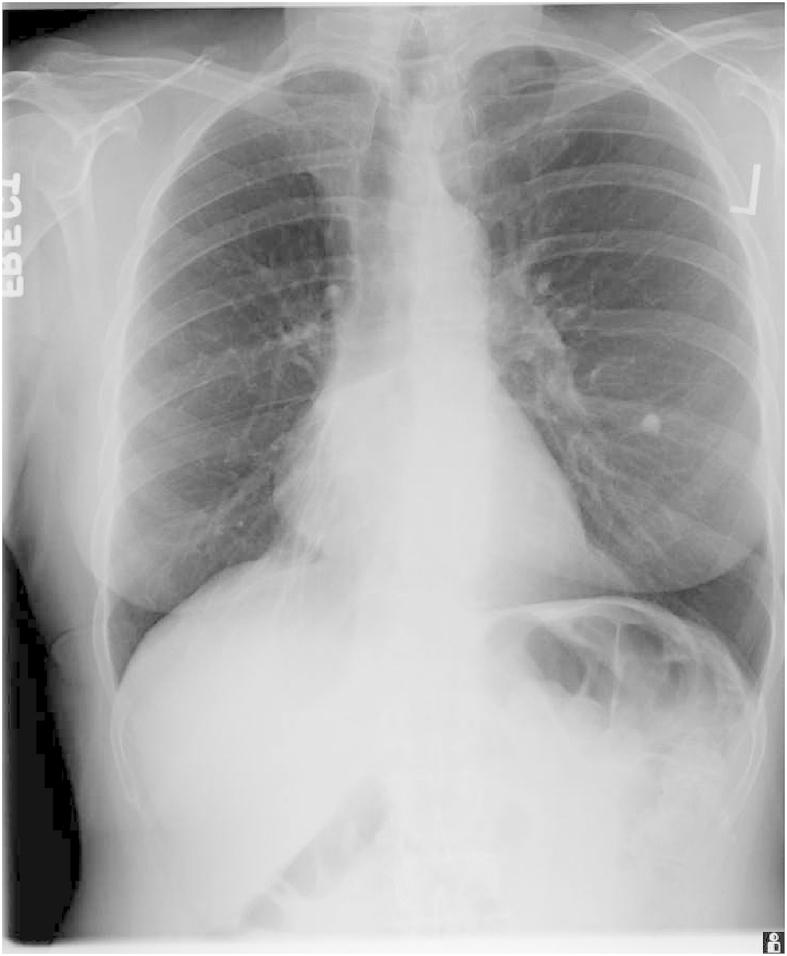

Chronic cough that is dry, non-productive and without constitutional symptoms is often thought to have a non-malignant etiology such as asthma, post-nasal drip or gastroesophageal reflux disease (GERD). We present a case of a patient with a 3 year history of 'chronic cough' that was dry, non-productive cough and without any constitutional symptoms. Initial chest x-ray (CXR) done 3 years ago showed some streaky atelectasis in the right middle lobe along with some volume loss on that side. Another CXR performed one and half years later showed progression to a complete right middle lobe collapse. She ultimately presented to our facility a year later with stable CXR findings, but persistent cough. A chest CT scan was suspicious for a right lower lobe mass. A PET scan subsequently confirmed a hypermetabolic right hilar mass causing extrinsic compression of the bronchus intermedius. She ultimately required a complete right pneumonectomy with partial pericardiectomy and had complete resolution of her cough. This case highlights the fact that 'chronic cough' should always be thoroughly investigated and should remain a diagnosis of exclusion until all sinister pathologies have been ruled out.

干咳、无痰且无全身症状的慢性咳嗽通常被认为病因非恶性,如哮喘、鼻后滴漏或胃食管反流病(GERD)。我们报告一例有3年“慢性咳嗽”病史的患者,其咳嗽为干咳、无痰,且无任何全身症状。3年前进行的首次胸部X线(CXR)检查显示右中叶有一些条索状肺不张,且该侧肺容积减小。一年半后进行的另一次胸部X线检查显示进展为完全性右中叶肺不张。一年后她最终到我们医院就诊,胸部X线检查结果稳定,但咳嗽持续。胸部CT扫描怀疑右下叶有肿块。随后的PET扫描证实右肺门有高代谢肿块,导致中间支气管外部受压。她最终需要进行全右肺切除术及部分心包切除术,咳嗽完全消失。该病例强调了一个事实,即对于“慢性咳嗽”应始终进行全面检查,在排除所有严重病变之前,应一直作为排除性诊断。